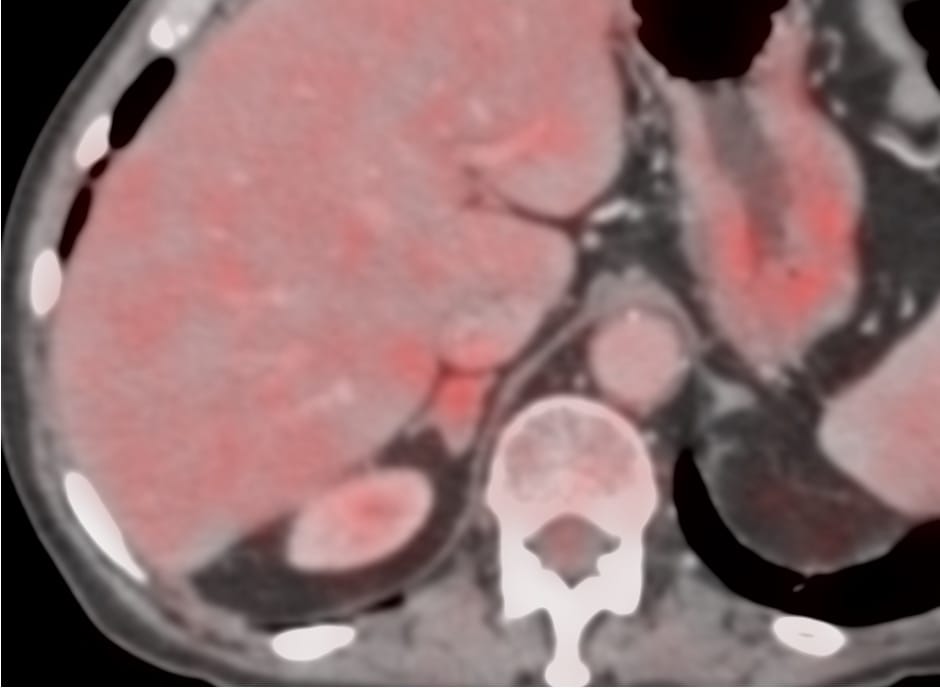

66-years old with treated lung cancer was found to have a right adrenal gland nodule.

Region: Adrenal Gland

Findings: Right adrenal gland nodule

Size of Lesion: 16 mm z axis x 12.4 mm